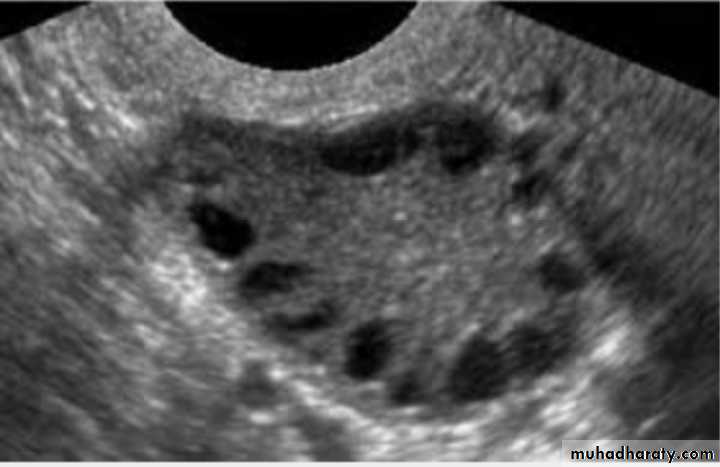

Pt. present with irregular vaginal bleeding , what is Dx? PCOS

Typical U/S finding in this case : bilateral ovaries containing multiple follicle more than 10 measure 2-9 mm diameter arranged in a neglict apperance with increase stromal thick and overian volum (>10cm3)

What other symptoms: 1-hisutims 2-infertility 3-obesity 4-acne 5-amenorrhea or oligomenorrhea

Lab. Finding :Increase serum LH

Increase serum LH : FSH ratio

Increase serum androgen (testosterone and androstenedione)

Decrease SHBG

Increase estradiol and estrone (not measured routinely as Very wide rang of values).

Increase serum prolactin.

Increase serum insulin level.

Impaired glucose tolerance .

U/S:PCOS